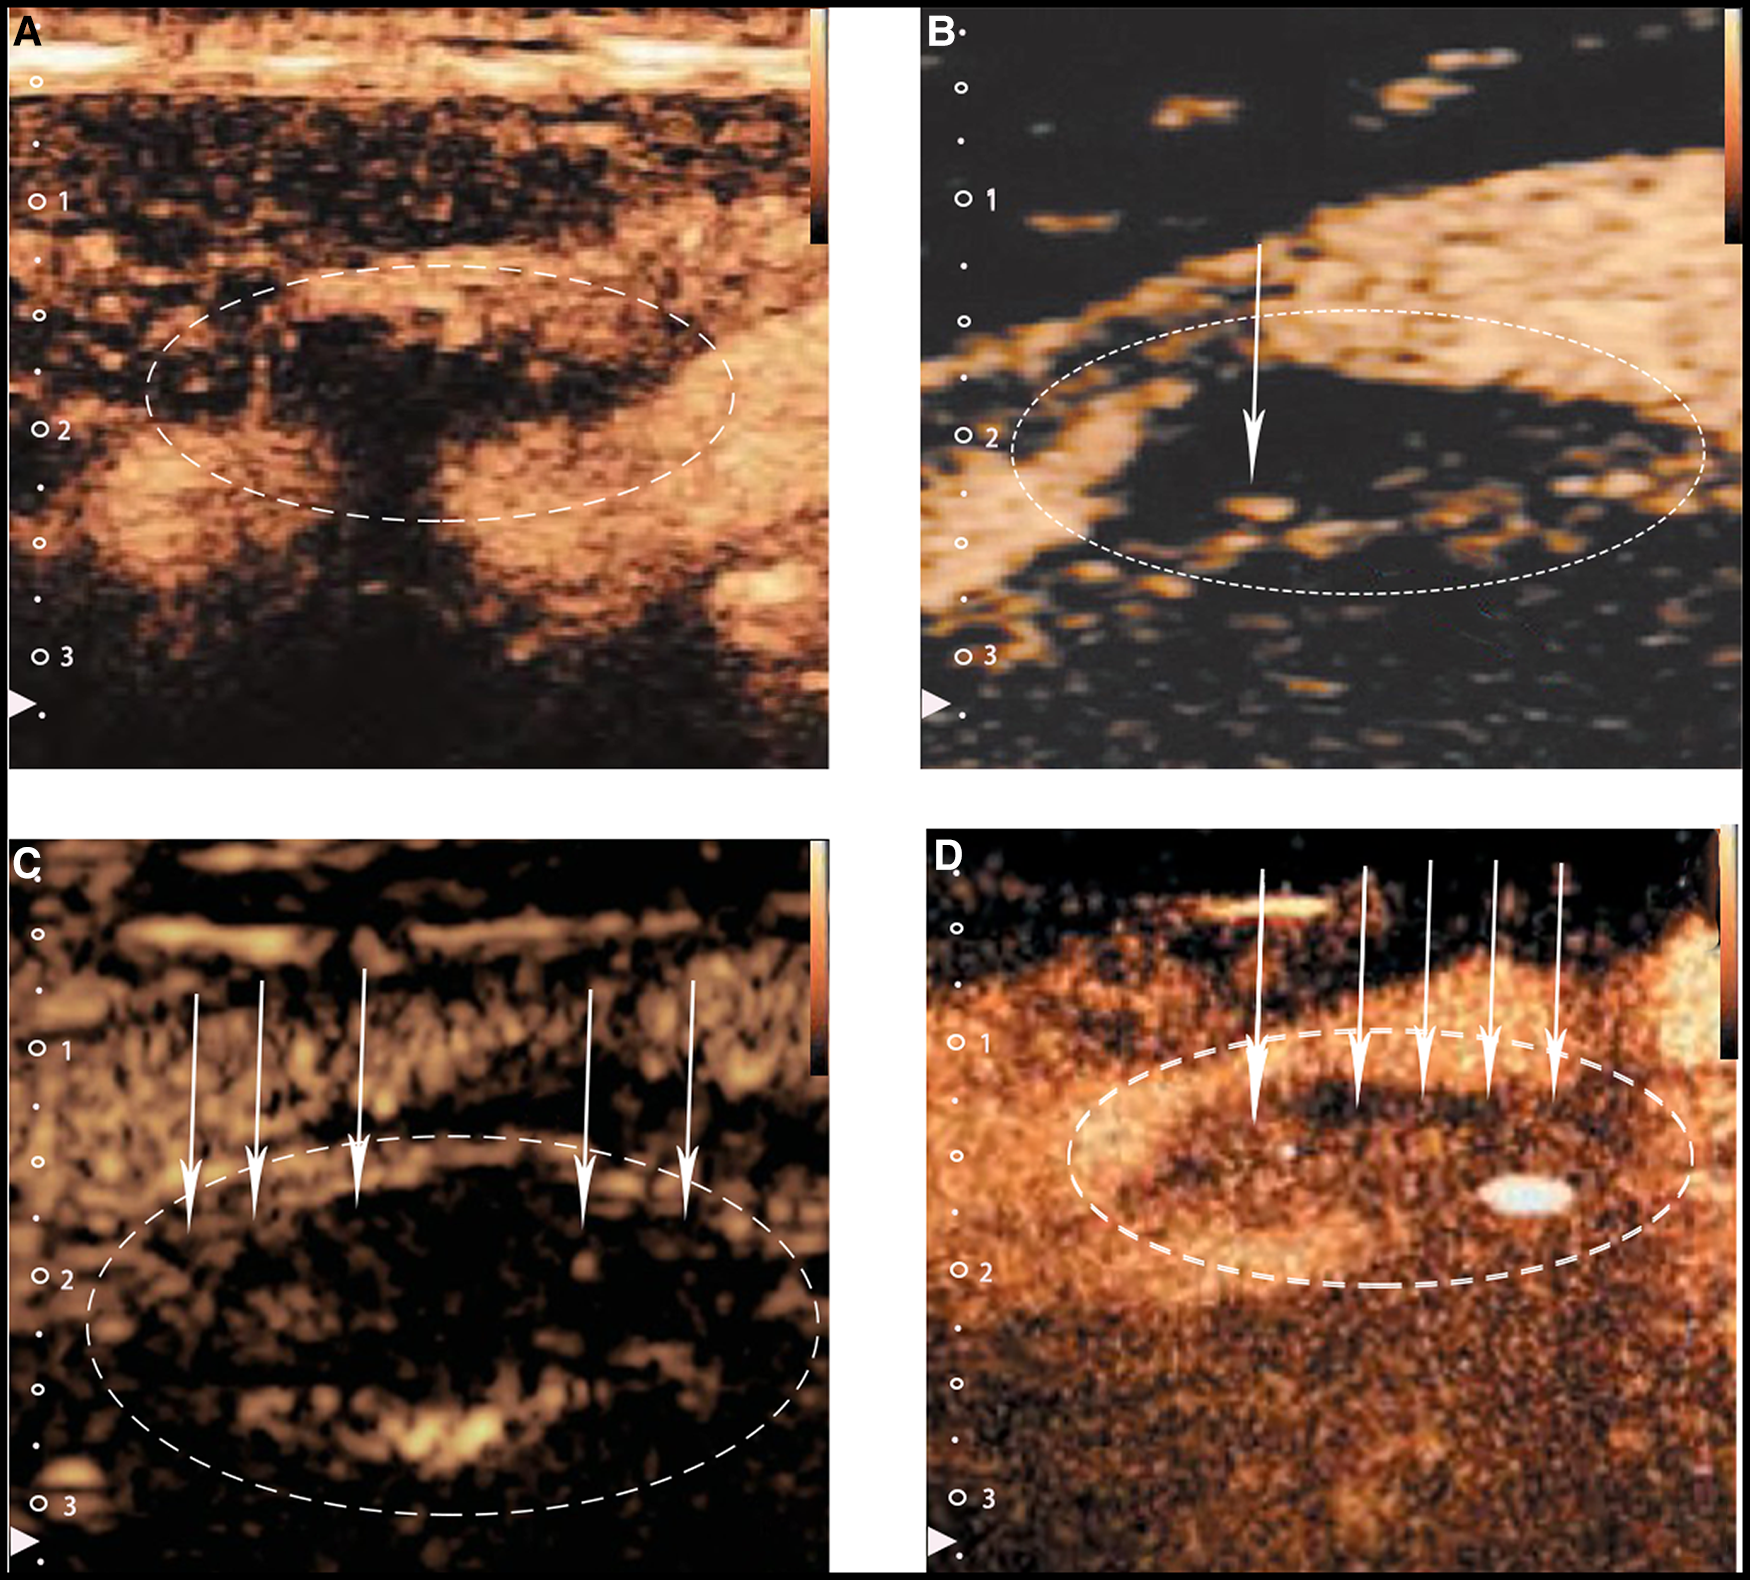

Figure 2

Typical CEUS images of carotid plaques. (Panel A) Shows no visible microbubbles in the plaque (grade 0). (Panels B,C) Show minimal microbubbles confined to the shoulder or the adventitial side of the plaque (grade 1). (Panel D) Shows plentiful microbubbles throughout the plaque (grade 2). The white arrows and dotted lines depict intraplaque contrast microbubbles.